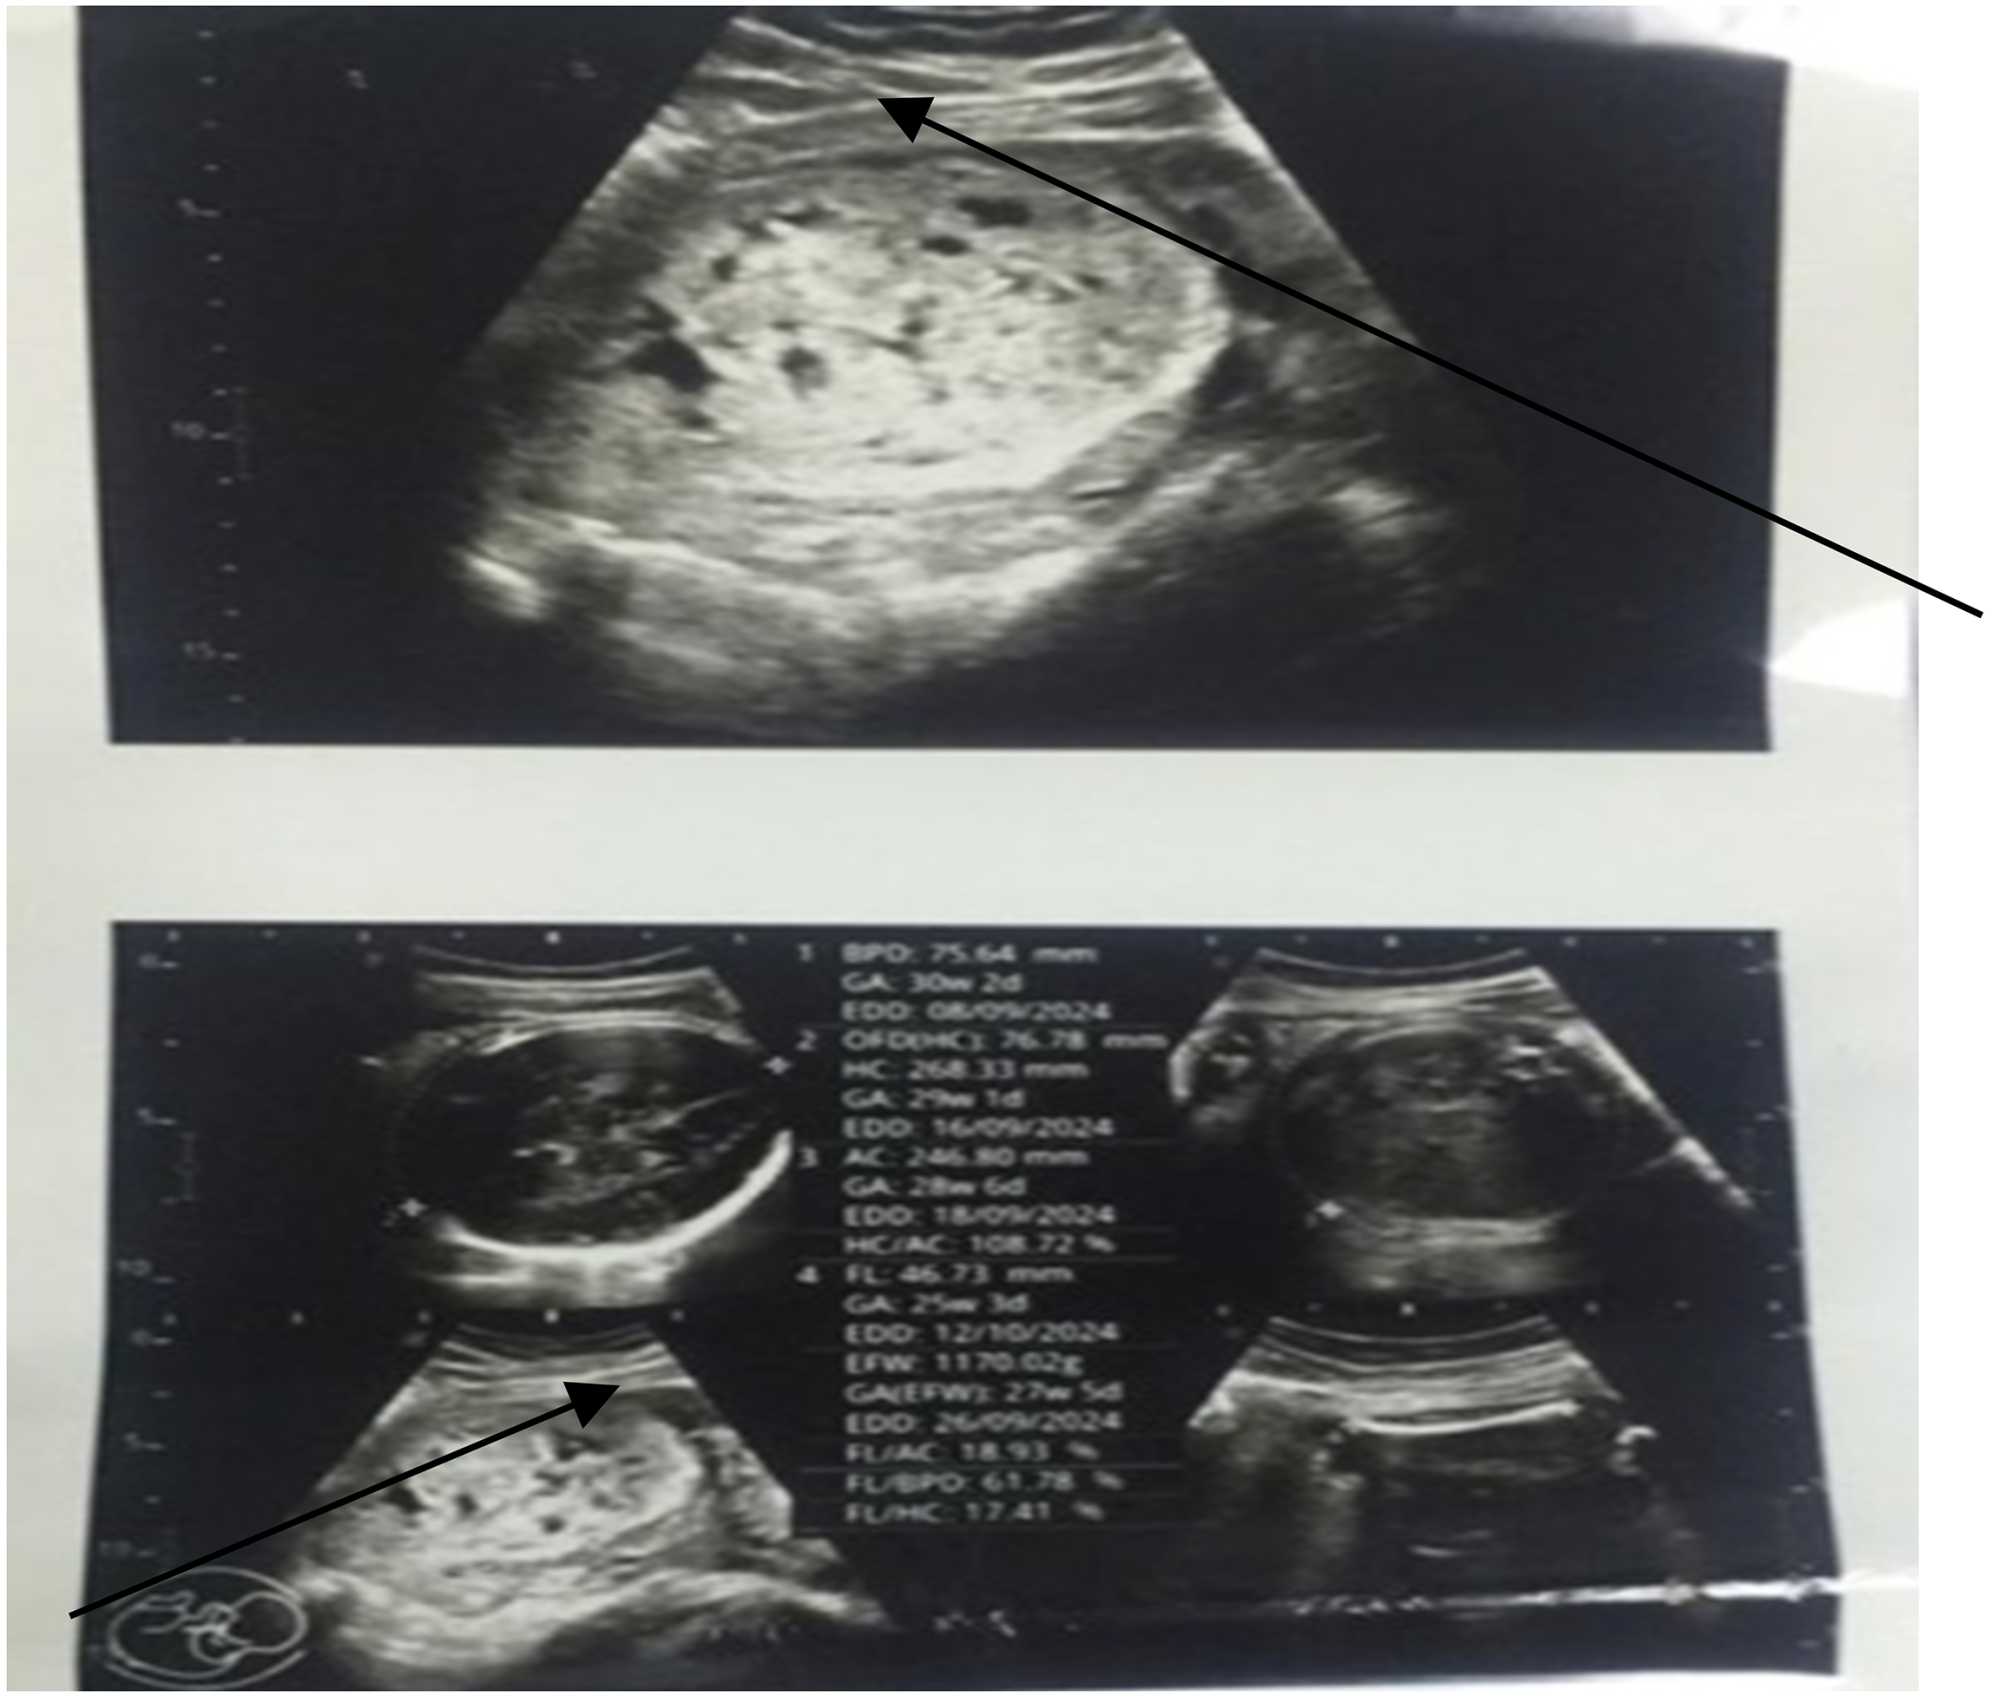

“We received a 28 – year old woman with an abdominal Pregnancy in our facility, whom we closely followed up to delivery. This is very rare representing 1% of ectopic pregnancies often associated with maternal mortality and fatal malformations. In our case, the mother and baby were closely followed up, well managed and they both went home in a stable state. The case illustrates that intra-abdominal pregnancies though rare and complex can be managed to term and produce visible fetuses”.